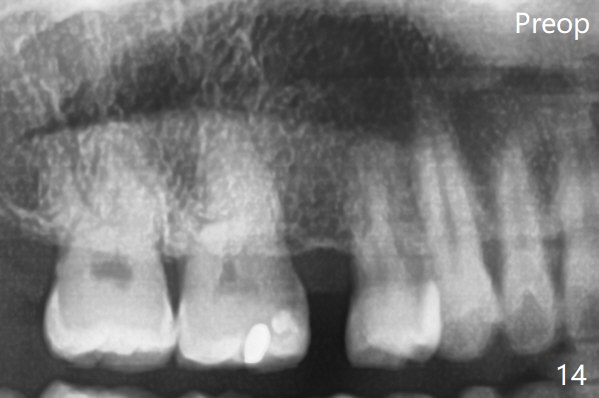

A 40-year-old man requests orthodontics after #17 and 32 extraction. UL5 is missing (Fig.1), while the upper midline deviates to the left (Fig.2 arrow) with crowding between UL2 and 3 (Fig.3). The main goal is to retract UL5 distal and move the upper midline to the right to alleviate UL anterior crowding. Implant will be not needed. To monitor potential root resorption associated with tooth movement, preop PAs are taken (Fig.4-7). The space for an implant at UR5 is narrow. UR4 needs to be distalized using UR7 or a miniimplant distal to UR7 as an anchor (Fig.8). UR4 and 3 will be repositioned to establish Class I occlusion (Fig.9). The space gained by UR4 distalization may be enough to correct the upper midline deviation and UL3 malposition (Fig.10). Brackets will be placed in the lower arch in spite of the normal alignment (Fig.11). UL2 and 3 brackets are unable to be engaged to 14 niti wire (Fig.12). Next visit try to engage UL2 bracket. If not, save the old wire for possible future reuse. Closed spring is placed with 18 ss wire <3 months post banding (coronavirus). Three weeks post closed spring between UR4-7, UR3,4 are being distalized (Fig.13). Distalization of UR4 is not much in 5.5 months (Fig.14,15). It seems necessary to use a miniimplant distal to UR7 as an anchor (Fig.16 white circle), place a long hook mesial to UL4 (more or less root movement instead of tilt) and place the same closed spring between the anchor and hook. In spite of the fact that UR4 seems to have been completely distalized and that UR2 is being distalized 8 months post banding (Fig.18), a 8 mm long mini-implant is placed in the maxillary tuberosity with minimal local anesthetic (Fig.17,19). A longer closed spring (18 mm) is placed between the implant and UR3 hook (Fig.20). Next appointment a lingual button will be placed at UR4 for rotation, while a post hook mesial to UR3 for torque. UR3 distalizes with the help of UR mini-implant, which is unfortunately loose. Next visit place lingual button at UR4 (Fig.21 arrow) to distalize the lingual cusp. Crimpable power hook is placed mesial to UR2 for distalization (for root torque, Fig.22). If it works, remove the wire and reposition the hook for UR1 next visit. UR2 is distalized in one appointment (~ 1 month, Fig.23, as compared to Fig.22). With lingual button at UR4, rotation seems to have been corrected shortly (Fig.24 arrow).